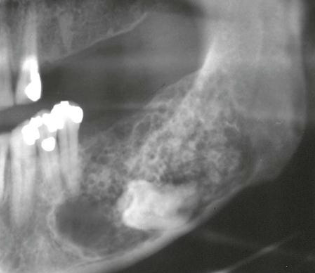

excessive growth of condyle; due to neoplasms and endocrine disturbances

condylar hyperplasia